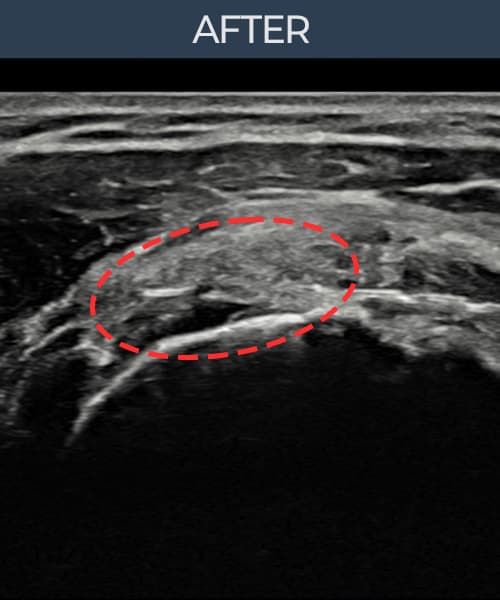

左侧 冈上肌腱 石灰化肌腱炎

9mm × 7mm